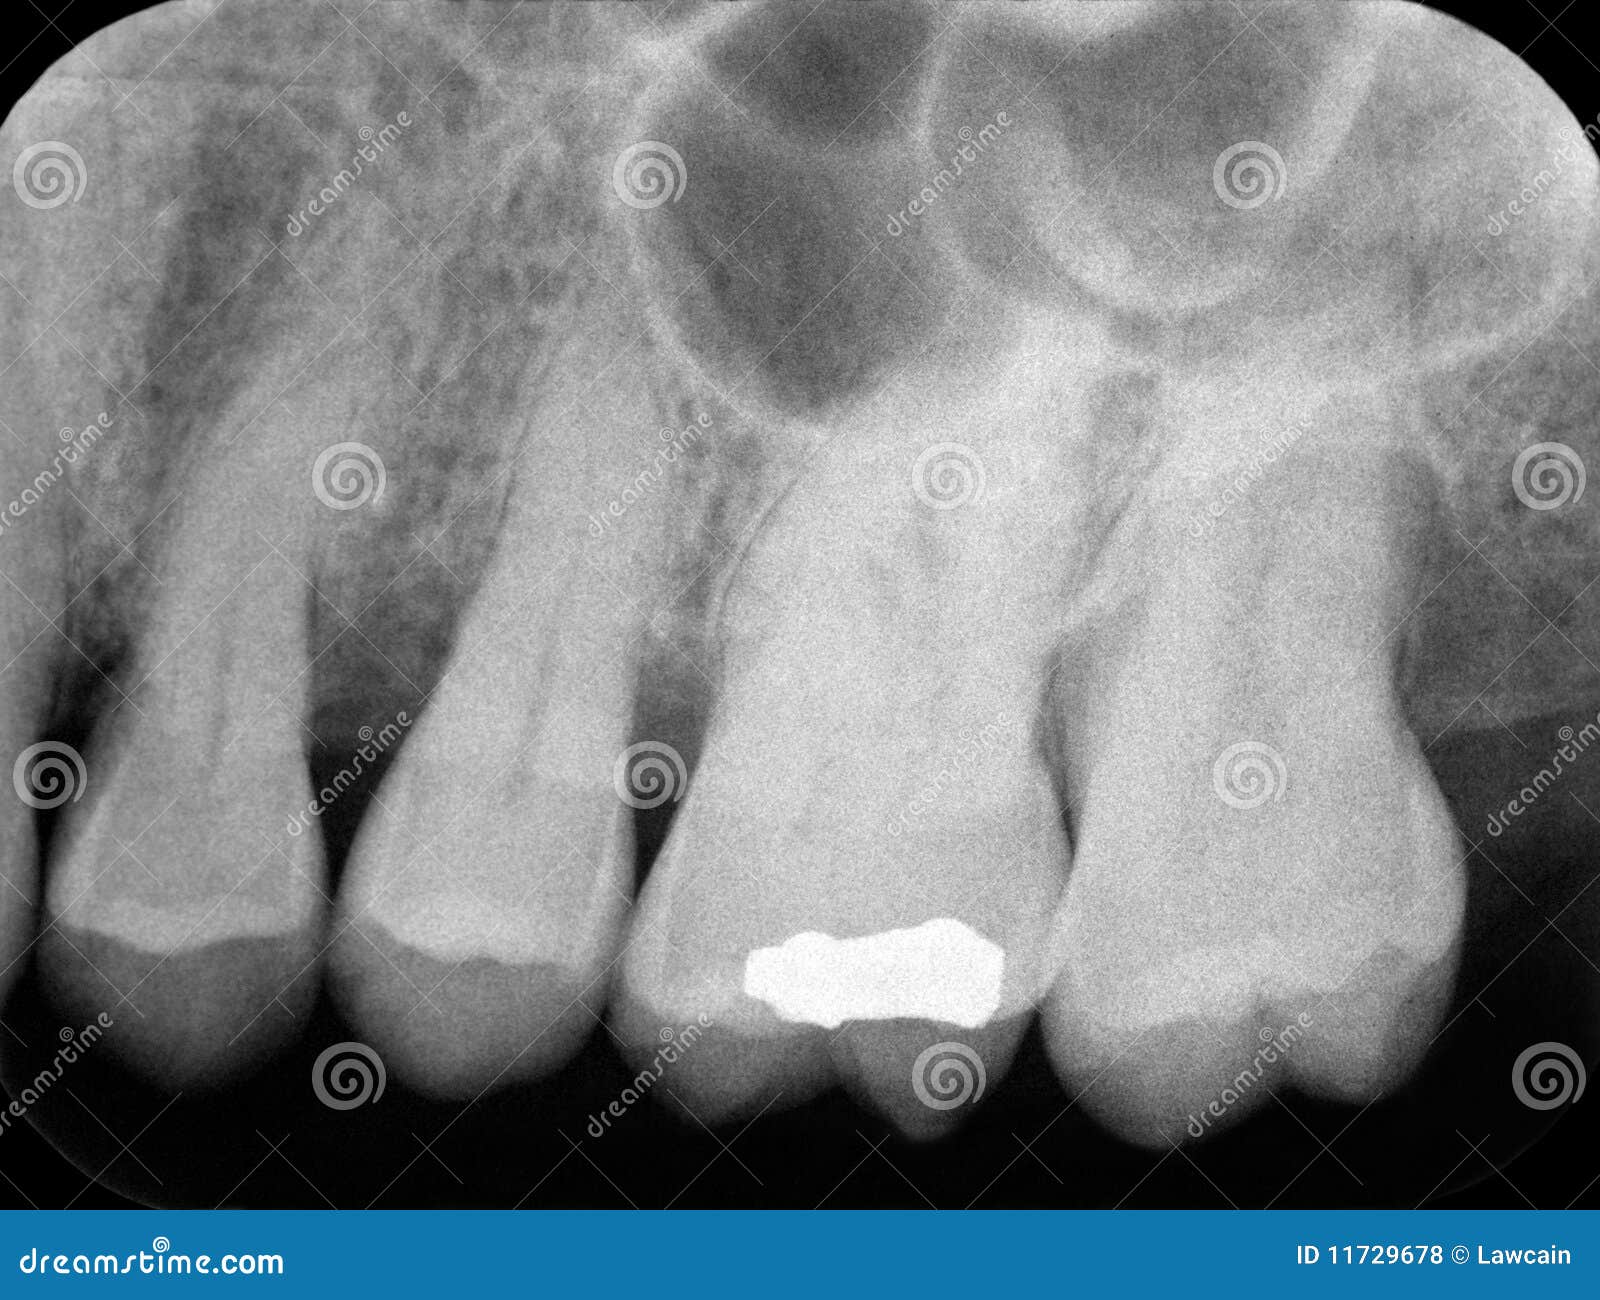

Dental Bone Loss Xray . When evaluating the staging of periodontal disease, categorized on a scale from 1 to 4, it is essential to consider several. Additional intraoral films might be helpful where. When identifying horizontal bone loss. If you have significant bone loss, your dentist can use regenerative bone grafting to supplement the bone surrounding your teeth. This week is all about the basics of horizontal bone loss and vertical bone defects on radiographs. This allows the surgeon to place dental implants to replace and restore missing or lost teeth. Your dentist may assign a stage and a. A preorientation with respect to the expected bone loss is possible using panoramic radiographs.

This week is all about the basics of horizontal bone loss and vertical bone defects on radiographs. Additional intraoral films might be helpful where. When evaluating the staging of periodontal disease, categorized on a scale from 1 to 4, it is essential to consider several. When identifying horizontal bone loss. A preorientation with respect to the expected bone loss is possible using panoramic radiographs. If you have significant bone loss, your dentist can use regenerative bone grafting to supplement the bone surrounding your teeth. This allows the surgeon to place dental implants to replace and restore missing or lost teeth. Your dentist may assign a stage and a.

Dental Bone Loss Xray This allows the surgeon to place dental implants to replace and restore missing or lost teeth. Additional intraoral films might be helpful where. This allows the surgeon to place dental implants to replace and restore missing or lost teeth. Your dentist may assign a stage and a. A preorientation with respect to the expected bone loss is possible using panoramic radiographs. When evaluating the staging of periodontal disease, categorized on a scale from 1 to 4, it is essential to consider several. If you have significant bone loss, your dentist can use regenerative bone grafting to supplement the bone surrounding your teeth. This week is all about the basics of horizontal bone loss and vertical bone defects on radiographs. When identifying horizontal bone loss.